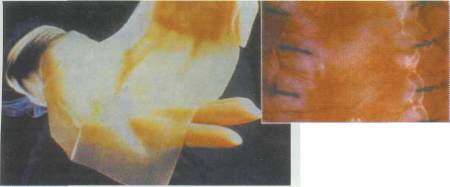

Tüm damar yapılarını da içeren üç boyutlu kalın bir karaciğer oluşturma fikri 5-6 yıl öncesine kadar yalnızca bir hayal olarak kabul ediliyordu. Dr. Vacanti'nin 1997 yılında bir farenin sırtında insan kulağı geliştirdiği günden beri, üç boyutlu ve damarlı yapay karaciğer fikri hayal olmaktan çıktı. Harvard Üniversitesi'ndeki bilim

adamları orijinal karaciğer benzeri bir model oluşturdular. Yapay karaciğer yaratmada en önemli basamak, karmaşık damar yapısını oluşturmak. Bu nedenle ilk olarak, vücuttan çıkartılmış bir karaciğerin damarlarının içine, özel bir sıvı plastik materyal enjekte ediliyor. Bu sıvı kısa süre içinde katılaşarak damarların şeklini alıyor. Daha sonra karaciğer dokusu özel sıvılarla eritilerek yok ediliyor. Geriye yalnızca katılaşmış ve damar şeklini almış olan madde kalıyor. Kurumuş ağaç dallarına benzeyen bu yapı, karaciğerin damar yapısını temsil ediyor. Bu yapının görüntüleri bilgisayara aktarılarak üç boyutlu görüntüler elde ediliyor. Bu görüntüler yardımıyla silikon kalıplar hazırlanıyor. Silikon kalıpların içine polilaktik glikolik asit (PLGA) yapısındaki bir madde dökülüyor. Böylece karaciğer

damarlarının organik bir iskeleti oluşturuluyor. Bu iskeleti oluşturduktan sonraki aşamaysa hücrelerin oluşturulması. Damar iskeleti çevresine yerleştirilen karaciğer hücreleri, belirli büyüme faktörleri yardımıyla çoğalarak organın kalın etli kısmını oluşturuyorlar. Bir sonraki aşamaysa damarın oluşturulması. Bunun için süngerimsi yapıda olan PLGA içine damar hücreleri enjekte ediliyor. İskelet, hücrelerin çoğalması için gerekli büyüme faktörlerini ve besin maddelerini içeriyor. Damar hücreleri iskelet boyunca ilerleyerek karaciğer hücrelerine yapışıyor. Burada çoğalan damar hücreleri, iskelet çevresinde birleşerek tam bir damar yapısı oluşturuyorlar. PLGA iskelet birkaç ay içinde kendiliğinden eriyerek geride karaciğer hücreleri ve içinde damarları olan yapay bir organ bırakıyor. Bu şekilde oluşturulan yapay karaciğer hayvanlarda denendi. Oldukça iyi kan akımının sağlandığı bu organlarda dışarı kan sızıntısı da gözlenmedi.